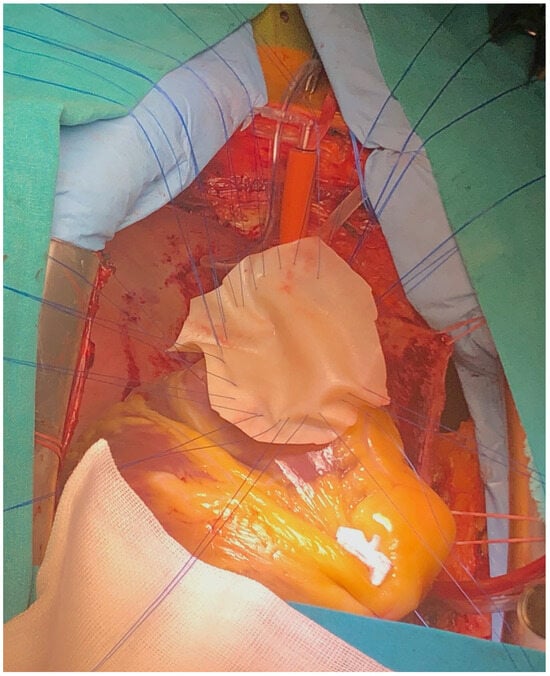

The surgery was carried out under general anesthesia, with iv induction and inhaled sevoflurane maintenance and total iv anesthesia during CPB. After median sternotomy, bicaval CPB was started, and the heart was arrested using anterograde and retrograde cold blood cardioplegia. After snaring both venae cava, the heart was enucleated with a 3.0 polypropylene stitch at the apex. A 10 cm incision was made on the posterior surface of the left ventricle, 2 mm parallel to the posterior interventricular artery. The margins of the VSD were identified. Interrupted matrass sutures of 2.0 Tevdek were placed circumferentially around the defect and used to secure a 4 × 7 cm bovine pericardial patch. The posterior papillary muscle was retracted into the sutures, so the mitral valve was replaced with a 27 biological prosthesis with preservation of the sub-valvular apparatus. The left ventriculotomy was closed with a double layer surjet suture, reinforced with Teflon felts. Details with surgical technique are shown in Figure 5, Figure 6, Figure 7 and Figure 8.

Figure 6. Surgical technique detail—large bovine pericardium patch.